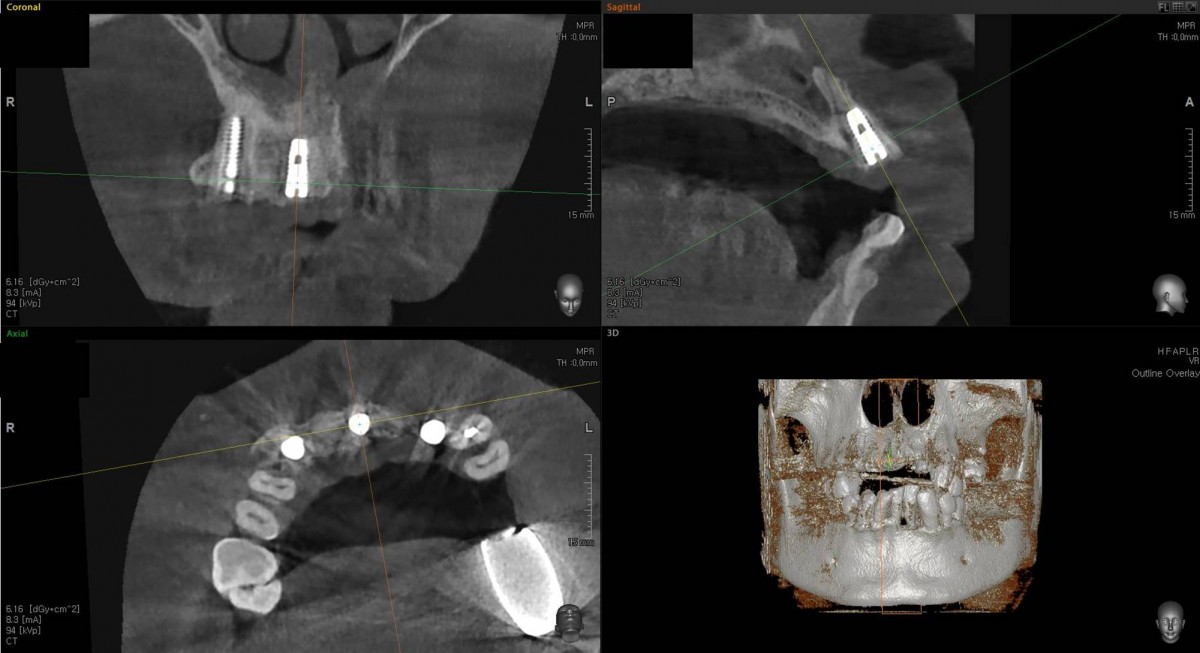

<GCpbc> A 58-year-old male is a patient undergoing implant installation in various parts. The old Br of the anterior maxilla has fallen

off and it is no longer possible to maintain it even temporarily, so a

treatment plan for the anterior teeth was made.